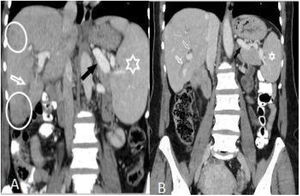

After treatment, the complete recovery of liver lesions was detected in 18 patients. Patchy hypodense areas were seen in 7 patients, microtubular abscess in 6 (Fig. 2), sequele calcification in 4, and abscess larger than 3cm in remained one patient (Fig. 3). The incidence of microtubular abscess and abscess >3cm was significantly lower in post-treatment images (p<.05). But, a non-significant increase in patchy hypodense area incidence was found on post-treatment images (Table 2).

On the first scans, frequency of four or fewer segments involvement (n:28, 77.8%) was markedly higher than of five or more (n:8, 22.2%) (p: .001) (Table 1, Fig. 5). Most commonly three (n:8, 22.2%) and four (n:8, 22.8%) segments involvement were observed while five (n:1, 2.8%) and seven (n:1, 2.8%) segments involvement were rarest. After treatment, hepatic involvement was not seen in 18 of 36 patients. Among those 18 patients, 11 (61.1%) had one (n:6) or two (n:5) involved segments. The average involved segment number of the 36 patients was 3.50±1.96 before treatment, which was significantly higher than after treatment (1.22±0.52) (p: .001). Segmental involvement features are detailed in Fig. 5.

During the migration of parasites, multiple millimeter confluent abscesses are formed.14 Abscesses are best seen in portal venous phase CT scans because they do not show internal contrast enhancement and can be easily identified in normal contrasting liver parenchyma.5,15 In a study that included 22 patients, six months after the treatment, they found complete clinical and laboratory improvement in all patients, complete recovery in 16 (73%) patients, and residual hypodense lesions in 6 (27%) patients on CT examinations.9 In a different study, during a long-term follow-up, sequele calcification in liver parenchyma was seen in 6 (9%) of the patients.12 In our study, 30 (83.3%) patients had microtubular abscess, 9 (25%) abscess larger than 3cm and 5 (13.8%) patchy hypodense areas. In 10 (29.7%) patients, there was edema or thickening in the intrahepatic biliary tract, and in 29 (80.6%), perihepatic minimal density was observed in the pretreatment CT scans. Clinical and laboratory improvement was observed in all patients. We detected complete improvement in liver parenchyma lesions in 18 (50%) patients after treatment and sequele calcification in 4 (11.1%) patients.

A minimal amount of perihepatic or subcapsular fluid was reported in 4 patients (5%) among 87 patients with fascioliasis in literature.12 In another study, perihepatic fluid accumulation was detected in 9% of the patients with fascioliasis.9 We detected perihepatic or free intra-abdominal fluid in 22.2% of our patients in the initial CT scan, and after the treatment all these fluids disappeared. Although subcapsular bleeding is not a common finding in fascioliasis, it is suggested that F. hepatica parasites may rarely cause a focal hematoma when crossing the liver capsule in different studies in the literature.10,17,18 We detected subcapsular hematoma in segment VI in only one patient, which markedly regressed during the follow-up at 24 months after the treatment. Also in two patients, we observed perihepatic or intraperitoneal high-density (30HU) free fluid compatible with hemorrhages, totally disappeared after the treatment.